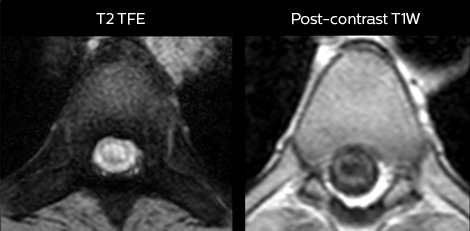

Including mDIXON TSE for robust fat suppression

“We use mDIXON TSE extensively in our spine imaging in the emergency room,” says Dr. Karis. “It’s particularly nice in that it is very robust with regard to susceptibility type of problems that would come up with traditional spectral fat-saturated images; these problems are essentially eliminated with the mDIXON technique. In our ED environment it’s really nice to have the fat-free imaging that goes along with the mDIXON technique.

“For the thoracic and cervical spine routine non-contrast exam, for example, we perform one mDIXON T2 TSE sequence, which provides us with two outputs: the fat-and-water-together T2-weighted images, as well as the water-only sagittal T2-weighted images. And then we also perform an axial gradient echo exam.”